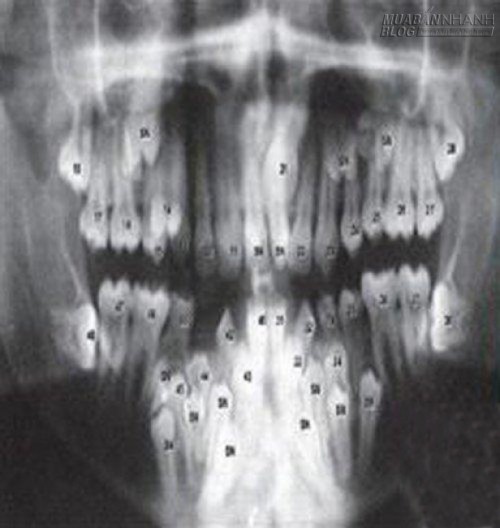

Bản phim X-quang cho thấy có vô số răng mọc trong miệng và không theo một trình tự nào